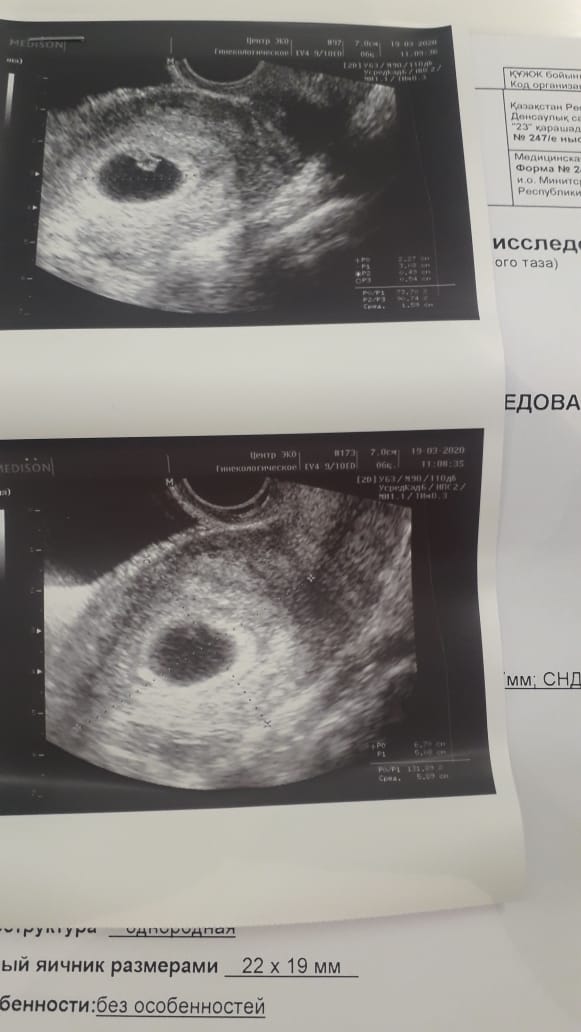

回国后的第二十八天,我们收到了第一份超声波报告。阿依古丽在邮件里写道:“胚胎着床位置良好,心跳正常。玛蒂娜的孕酮水平有点低,已开始补充——根据您添加的条款,我们优先保证她的健康。”

今天,孕24周的报告到了。超声波照片上,能清晰看见小手的轮廓。玛蒂娜在录音里用俄语说:“今天巴彦踢了我三次,很活泼。我告诉他,你妈妈在北京等你,她很爱你。”

窗外的北京正在飘柳絮,如雪,如时光。我摸着手机屏幕上的超声影像——不,是玛蒂娜腹中正在长大的生命——想起阿拉木图的那棵苹果树。